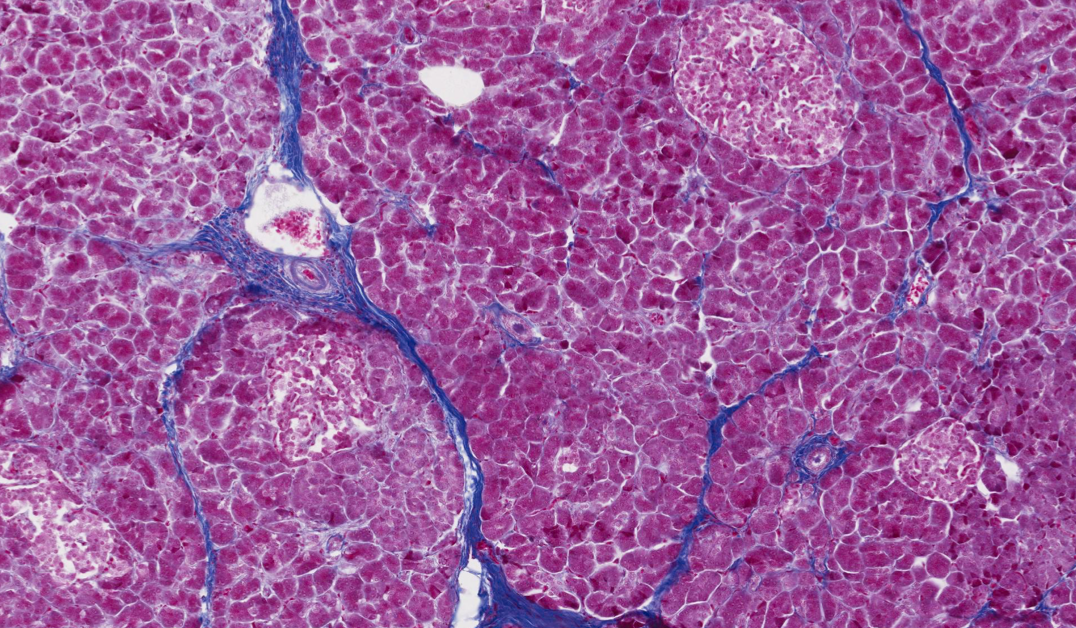

In some of the michigan collection slides, it is the only stain and therefore only elastin is demonstrated. The main point of the slide is to show you how much richer the vascular supply is to the endocrine tissue, the islets of langerhans, than to the surrounding exocrine pancreas. Anatomical terminology uses many unique terms, suffixes, and prefixes deriving from ancient greek and latin. These endocrine glands secrete hormones directly into the bloodstream and consist of three main cell types (alpha, beta, and delta) which. The conglomerations of gray matter deep within the cerebrum and cerebellum.

The main point of the slide is to show you how much richer the vascular supply is to the endocrine tissue, the islets of langerhans, than to the surrounding exocrine pancreas. Anatomical terminology uses many unique terms, suffixes, and prefixes deriving from ancient greek and latin. The tissues with an endocrine role within the pancreas exist as clusters of cells called pancreatic islets (also called islets of langerhans) that are distributed throughout the pancreas. Islets of langerhans are seen in the pancreas. Identify islets of langerhans within pancreatic tissue and explain the relative positions of alpha and beta cells. Don't worry, you don't need to know the entire greek alphabet to understand the functions of the pancreas! The conglomerations of gray matter deep within the cerebrum and cerebellum. The outer part of the brain is gray matter called the cortex.

The outer part of the brain is gray matter called the cortex. The tissues with an endocrine role within the pancreas exist as clusters of cells called pancreatic islets (also called islets of langerhans) that are distributed throughout the pancreas. Look at the vascular perfusion of islets of langerhans. Pancreatic islets contain alpha cells , beta cells , and delta cells , each of which releases a different hormone. The conglomerations of gray matter deep within the cerebrum and cerebellum. Don't worry, you don't need to know the entire greek alphabet to understand the functions of the pancreas! In some of the michigan collection slides, it is the only stain and therefore only elastin is demonstrated. It stains elastic fibers and granules of beta cells in the islets of langerhans, cartilage matrix, and stored neurosecretory product in the hypophyseal pars nervosa, among other things. Jun 17, 2021 · the endocrine function of the pancreas is carried out by the pancreatic islets of langerhans. Identify islets of langerhans within pancreatic tissue and explain the relative positions of alpha and beta cells. The main point of the slide is to show you how much richer the vascular supply is to the endocrine tissue, the islets of langerhans, than to the surrounding exocrine pancreas. Soma is another term for a neuron cell body. Before histological preparation, the arterial supply of this pancreas was injected with a red material.